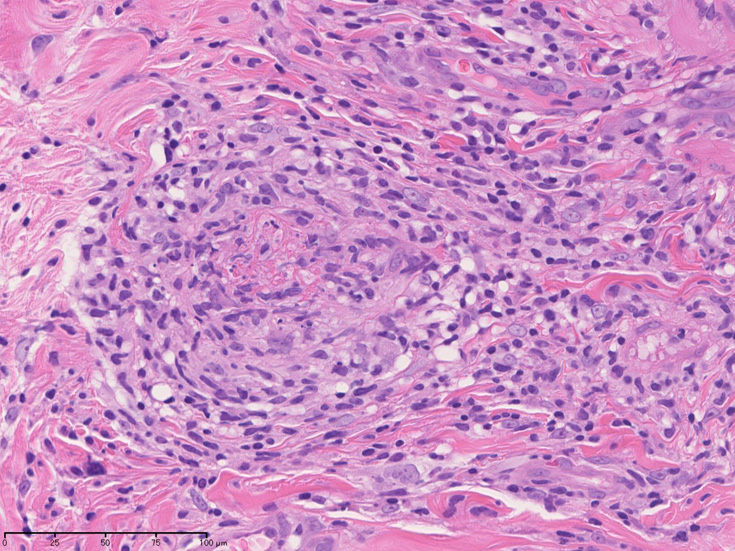

皮膚の血管(静脈・細動脈)病変、脂肪織炎 (サムネイルをクリックすると大きな画像が見られます)

Bec01.jpg

fibrinoidnecrosis01.jpg

vasculitisYa.jpg

fibrinoid necrosis

obstruction.jpg

免疫染色:血管腔を閉塞する細胞の多くはCD68, CD163陽性細胞. CD34陽性内皮が保たれている。